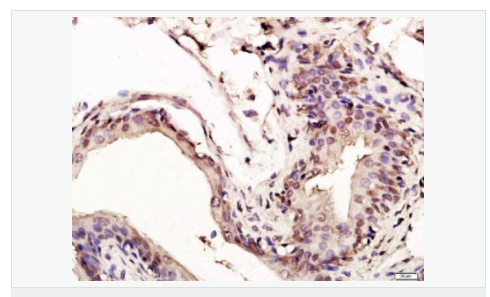

| 產(chǎn)品應(yīng)用 | WB=1:1000-2000 ELISA=1:1000-5000 IHC-P=1:100-500 IHC-F=1:100-500 Flow-Cyt=1ug/Test ICC=1:100-500 IF=1:100-500 (石蠟切片需做抗原修復(fù)) not yet tested in other applications. optimal dilutions/concentrations should be determined by the end user. |